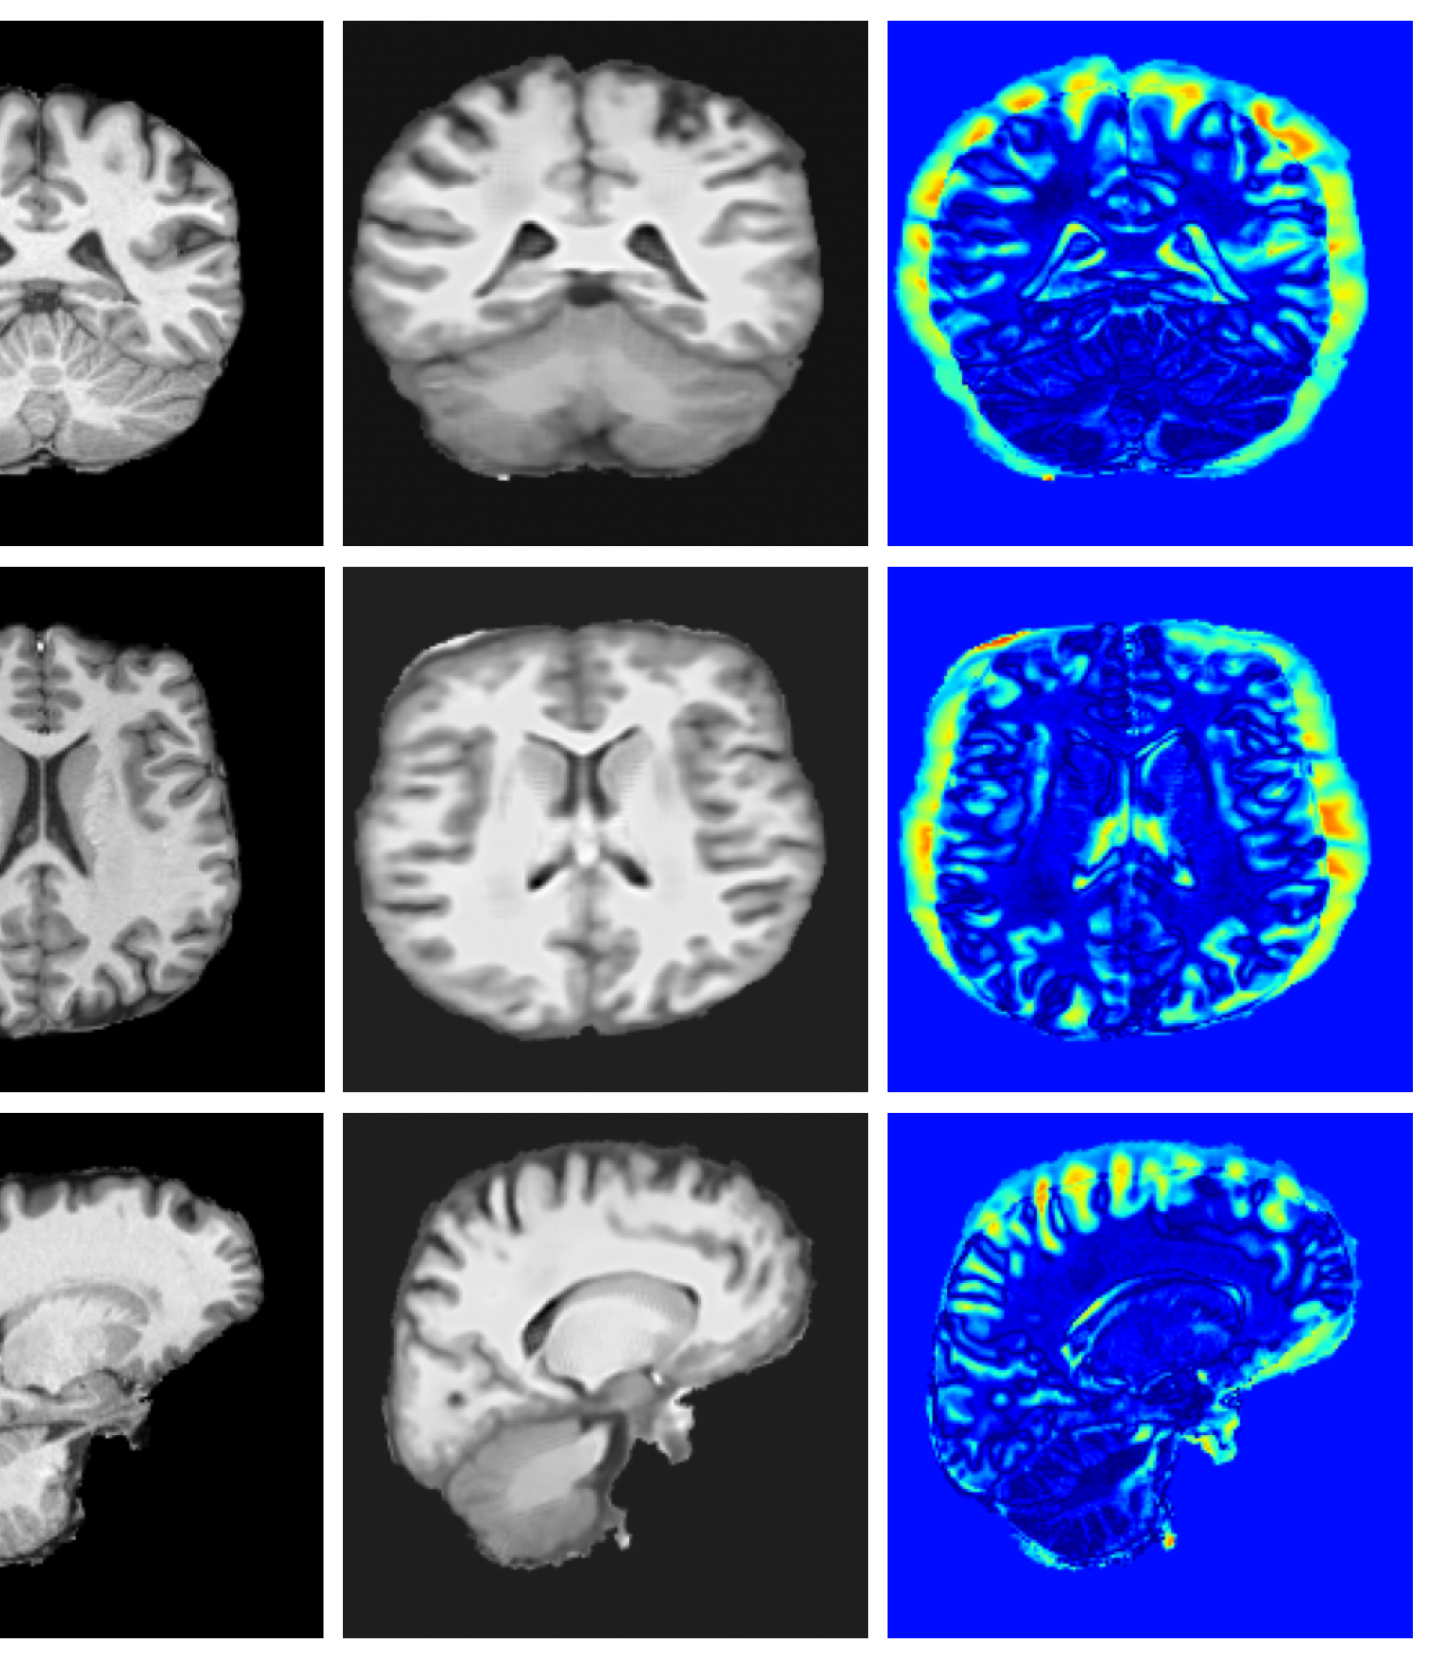

Image refinement. Many existing image processing tools provide approximate solutions that could benefit from further refinement. While these methods have proven valuable for processing heterogeneous data, their outputs often exhibit characteristic artifacts such as over-smoothing of fine details or inconsistencies with the underlying morphology. For example, SynthSR Iglesias2023 can fail to fully inpaint pathology or smooths images. Our diffusion-based inverse problem framework provides a principled approach to refine outputs from any existing method by treating them as initial approximations that can be iteratively improved. We formulate this as a constrained reconstruction problem where we seek to generate a high-quality image that maintains consistency with the initial approximation from the existing method. We construct the likelihood and posterior:

| (16) |

where controls the trust placed in the initial approximation.

4.4 Image refinement results

The image refinement results (see Appendix A.10 for more examples) in Figure 4 highlight our framework’s ability to enhance outputs from existing methods. While SynthSR can inpaint disease regions, the resulting tissue often appears unrealistic. Our method further refines these areas, producing anatomically plausible reconstructions with more realistic surface structures.

A.10 Additional qualitative refinement results

Additional qualitative refinement results for subjects from the ATLAS dataset are given in Figure 14